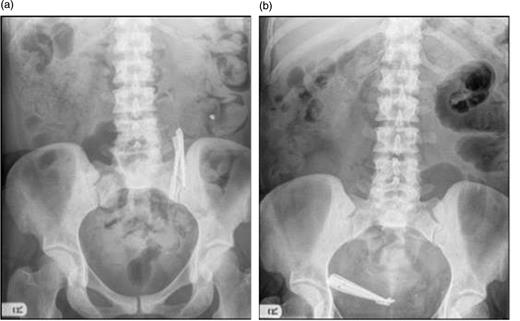

The patient was stabilized and recalled for surgical removal of the foreign body the following week: a laparotomy under general anaesthesia was performed and the foreign body removed via an enterotomy without complication (Fig. 2a). The post-operative course of the patient was uneventful.

(a) Foreign bodies following removal from small bowel (note faecolith). (b) Foreign bodies after faecolith removal.

A delay in the presentation of an ingested foreign body is a rarity, with only 40 cases being identified in a PubMed search over the past 10 years, even fewer of which were delayed as long as 5 years. This, as such, is a relatively unexplored phenomenon. In our case, two main factors facilitated this protracted clinical course. Firstly, the scissors were both long (measuring 8 cm) and blunt (Fig. 2b). The longer an object the less likely it is that it will be able to pass through the meandering gut lumen, promoting stasis [1]. The blunt edges of the scissors reduced the likelihood of perforation, increasing the likelihood of presenting with bowel obstruction. Secondly, a faecolith formed around the scissor blades as they are an immobile surface. This serves not only to protect the bowel wall from the edges of the blade, but also expands with time, increasing the likelihood of bowel obstruction [2].